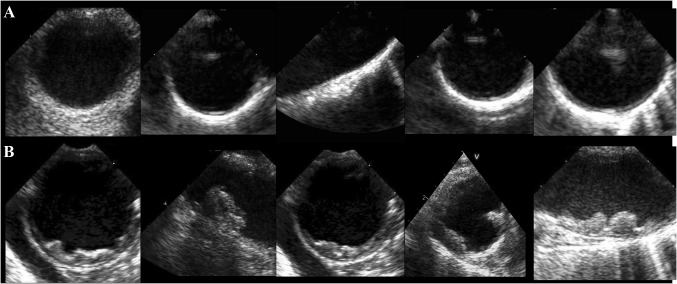

Fig. 2.

Representative image of patients with none or mild plaque (a) and with more than mild plaque (b: relevant plaque)